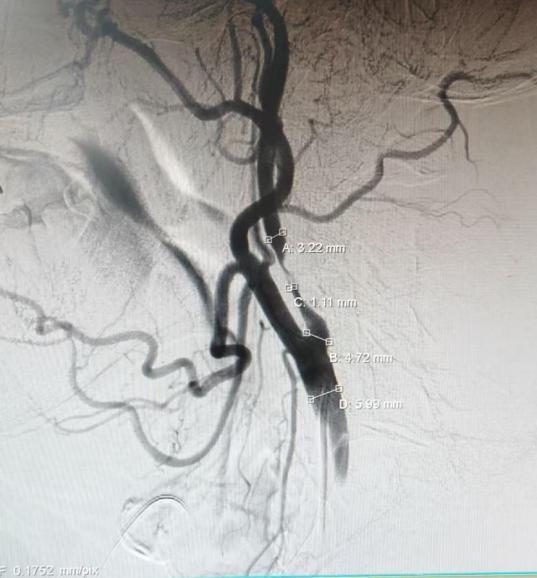

根据症状表现,急诊团队迅速启动卒中救治绿色通道,经快速评估并结合头颅CT、CTA检查,明确诊断王刚为“急性脑梗死”,且存在颈内动脉起始段急性闭塞狭窄,狭窄率高达96%。急诊团队立即联系神经外科卒中团队,并同步完成术前准备与静脉溶栓,争取为后续手术赢得宝贵的“时间窗”。

手术由神经外科(脑病一科)主任杨兴奎主导。在数字减影血管造影引导下,手术团队首先通过“颅内动脉取栓术”成功取出堵塞血管的血栓,实现血流初步再通。鉴于患者血管存在严重的动脉粥样硬化性狭窄,单纯取栓后血管很有可能再次闭塞。手术团队果断决策,继续对狭窄部位实施了“球囊扩张成形术”,并成功植入一枚颅内支架以维持血流通畅。术后造影显示,患者闭塞的脑血管血流恢复通畅,手术顺利完成。